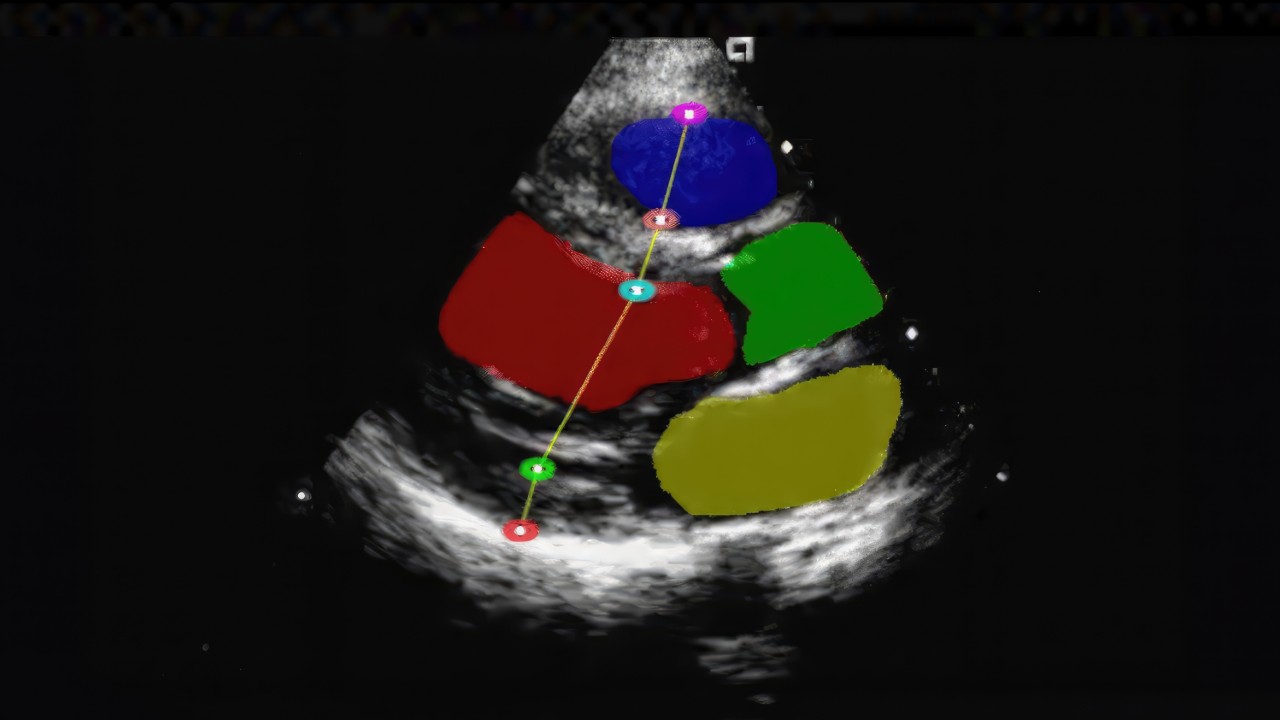

NVIDIA Holoscan is a versatile edge AI computing platform for real-time processing of streaming medical device data.

Medical device and AI application developers building medical device computing systems for platforms and sensor frontends can use Holoscan to build real-time AI at the clinical edge.

NVIDIA Holoscan Reference Applications and operators provide ready-to-use, customizable examples and components for building real-time, AI-enhanced sensor processing applications.

Medical device and AI developers looking to accelerate their development can use Holoscan Reference Applications to quickly build and deploy solutions across medical imaging, sensor processing, and edge computing.